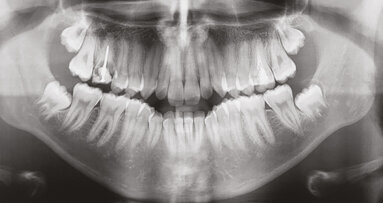

Dále byl vyhodnocen kefalometrický snímek (obr. 9), ortopantomogram (obr. 10) a provedena analýza modelů (obr. 11–15).